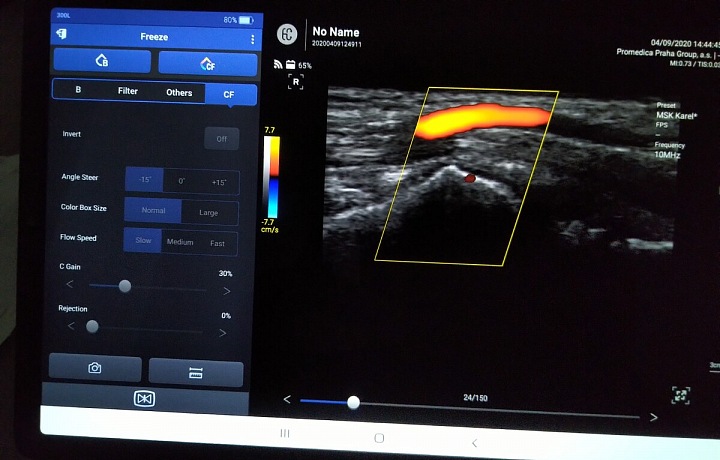

Obrazovka počítače při plicním skenování

Bezdrátová ultrazvuková sonda SONON

Bezdrátová ultrazvuková sonda SONONZdroj: Foto Jaroslav Urban

Pacienti, kteří nyní dorazí na plicní oddělení kladenské nemocnice, tak nejspíše čeká vyšetření novým plicním ultrazvukem. Jde o snadno přenosný, bezdrátový a malý přístroj, který však dokáže velké věci, a lékařům tak zásadně usnadnit práci.